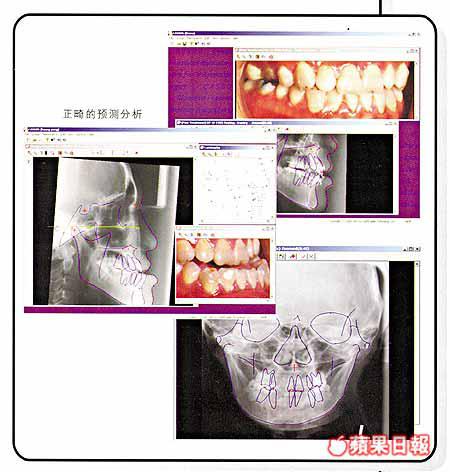

該系統是首個本土開發的手術模擬預測系統,為正頜外科提供全面的醫療記錄和圖像管理功能。

該綜合軟件系統不但高度互動而且簡單易用,可運行於個人電腦視窗作業系統上,具備為病人提供正面和側面的頭部測量分析、軟組織改變的預測,以及手術計劃編制等功能,讓醫生透過多個模擬預測,選擇最適當的面部骨骼移動手術方案。